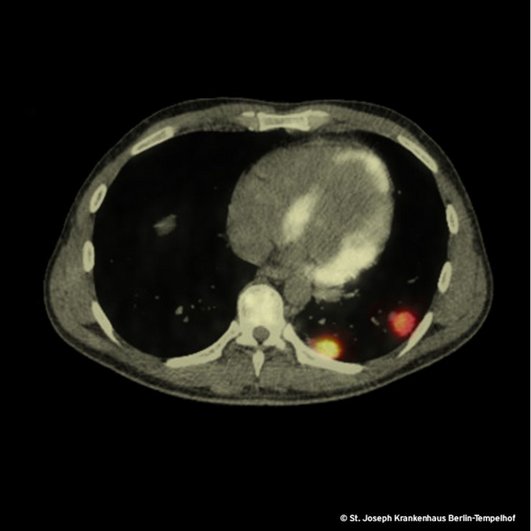

Der Verdacht auf eine maligne Erkrankung treibt uns zu einem PET-CT, welches 3 Wochen nach der Erstvorstellung eine schockierende Größenprogredienz der pulmonalen und vertebralen Läsionen enthüllt. Der Radiologe fällt das Urteil: bösartige hämatologische Systemerkrankung. Das Bild zeigt zwei der fünf pulmonalen Herde, die im PET-CT hohe Stoffwechselaktivität aufweisen.